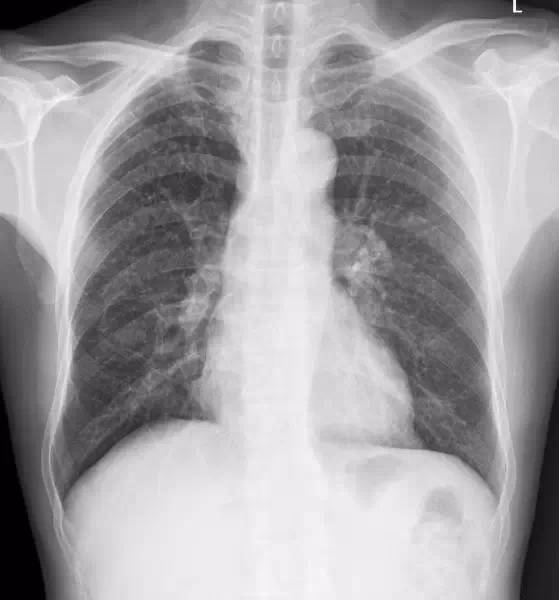

双肺纹理增多,双肺野散在多发细小结节影